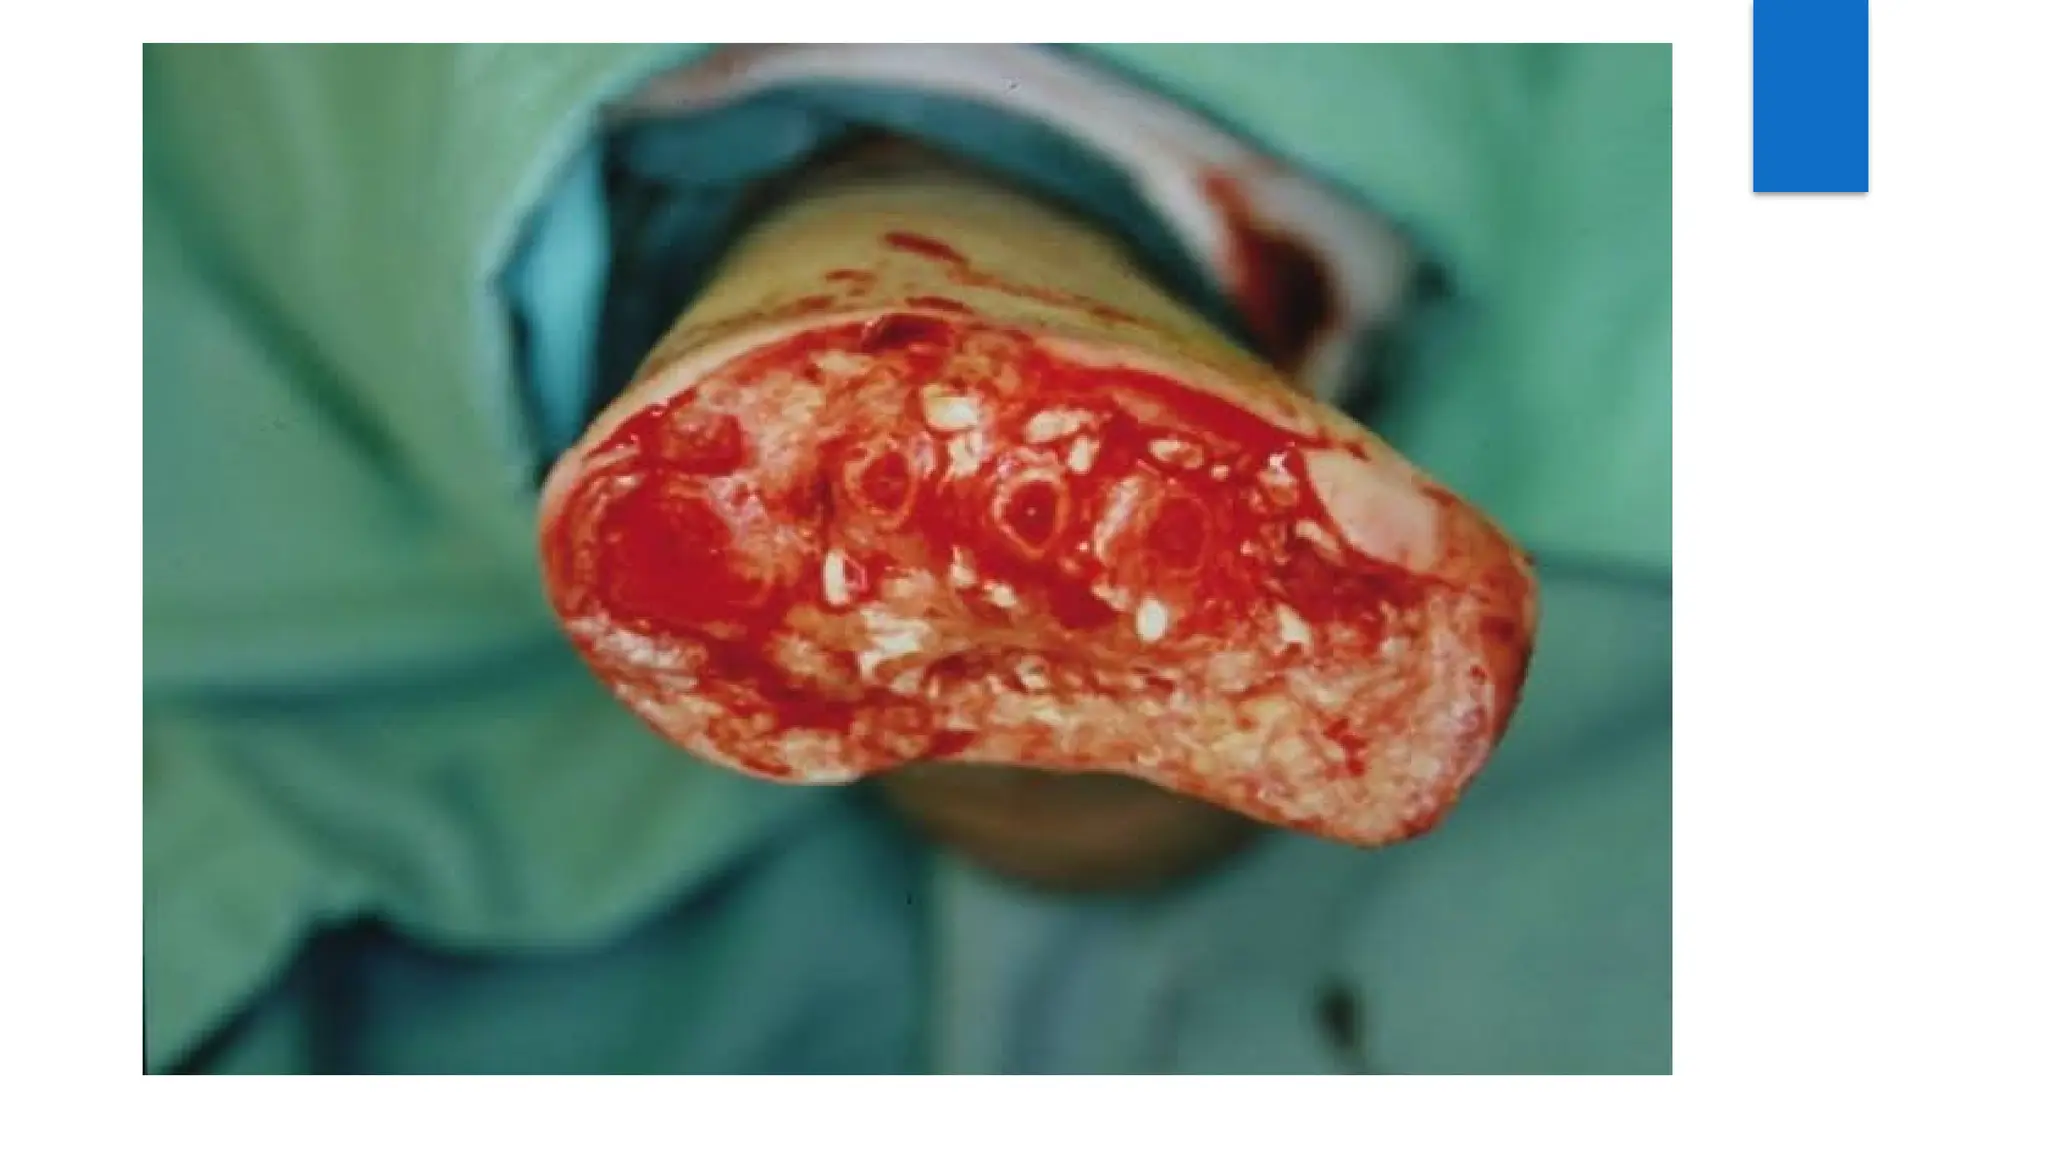

 Guillotine amputation or open amputation – It`s a emergency procedure

as a life-saving measure . In this , the skin is not closed over the

amputated stump . It is left open and dressed regularly till infection

subsides and stump becomes healthy . The operation is followed , after

some period , by one of the following procedure for constructing

satisfactory stump:

a. Secondary closure = Closure of skin flaps after few days